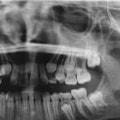

Dental X-rays, also known as radiographs, are an essential tool used by dentists to diagnose and treat oral health issues. These diagnostic images provide a detailed view of the teeth, jawbone, and other structures inside the mouth. X-rays can reveal areas of decay and infection that are not visible during a physical examination. Dental X-rays allow dentists to create detailed images that show individual tooth structure and bone growth as well as potential problems including bone loss due to gum disease, cavities between teeth, and even signs of impacted wisdom teeth.

The images produced by dental X-rays give dentists a better understanding of their patient's oral health status which allows them to develop effective treatment plans based on this information. By using cutting-edge technology such as digital radiography systems, today’s modern dentists can now access detailed images with less radiation exposure than traditional film processes used previously which helps ensure safety for all patients receiving dental care services.

Dental X-rays are an essential tool for dentists who wish to perform successful dental implant surgeries. The many ways dental x-rays can help a dentist diagnose the condition of your teeth or mouth are:

- Identifying the location of your teeth, as well as any potential issues such as decay or bone loss. X-rays can help a dentist determine the best placement for implants and identify any risk factors that may affect the success of an implant procedure.

- Checking for the presence of gum disease, which is a common cause of tooth loss and can affect the stability of dental implants if left untreated. X-rays are also useful in diagnosing infections within teeth or gums and assessing how much damage has already been done to areas where implant surgery would be performed.

- Evaluating existing restorations like crowns, fillings, and bridges to ensure they are properly aligned with adjacent teeth before implantation. This helps prevent the creation of an uneven bite and other problems that can occur if restorations are not placed correctly.

- Measuring bone density to determine if a patient is a strong enough candidate for implant surgery. X-rays also reveal if there’s enough bone available to securely place implants and hold them in place over time.

With the help of dental x-rays, dentists can make an accurate diagnosis and perform successful implant surgery to restore patients’ smiles. X-rays play a key role in helping dentists plan treatment, assess any potential risks or complications, and ensure that implants will have long-term stability and success.